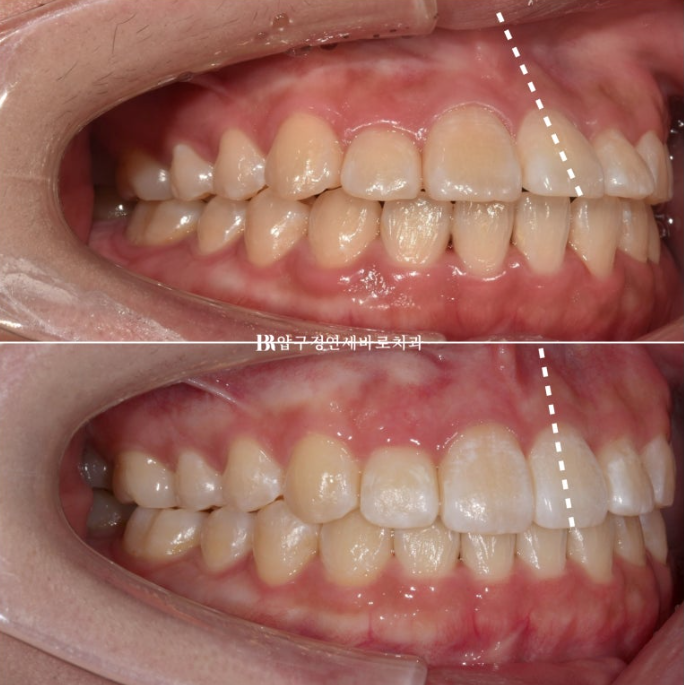

23.04~24.01

앞니 각도 전 후 변화입니다.

앞니가 상당량 후방이동 하며 입술도 뒤로 들어갔습니다.

치료 전 후 엑스레이 중첩을 보면 앞니 각도 개선이 두드러집니다.